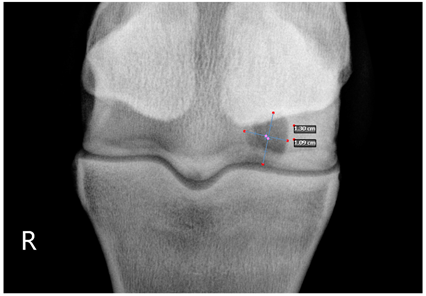

2.2. Image Analysis

Preoperative radiographs in DICOM format were evaluated blindly in a randomized order by three observers using medical imaging viewer software (OsiriX® Lite v12.0.1 DICOM viewer, Pixmeo SARL, Bernex, Switzerland). The width and height of the lesions were measured in dorsopalmar/plantar radiographic views. The magnification was corrected by calculating the index of the measured SCL with the total width of the specific joint affected. Each measurement was taken once by three authors. The mean of the three different measurements was calculated and used for statistical purposes. SCL shape was classified in three categories, following previous classification guidelines (Table 1 and Table 2) [8]. The intraclass correlation coefficient was calculated to make sure that there was a high level of agreement between observers when taking height and width measurements and when classifying SCLs by shape.

The median and interquartile ratios of the SCL height and width were 9.47 mm (6.97–10.92 mm) and 8.58 mm (6.98–10.96 mm), respectively. The SCLs located in the distal metacarpal/metatarsal bones measured 9.03 mm (6.96–10.9 mm) in height and 8.52 mm (7–10.92 mm) in width. A more oval shape was found in the lesions of the proximal phalanx, with a median height of 10.8 mm (7.03–10.95 mm) and a median width of 7.78 mm (7.09–10.96 mm). A rounder shape was found in the distal phalanx, with a median of 10.28 mm (7.05–10.97 mm) for height and 10.81 mm (7.03–10.95 mm) for width. The different bones affected by the SCLs were no different in the horse’s ability to start a race (p = 0.33).

Table 1. Radiographic appearance and shape classification into 3 types of subchondral lucencies based on their shape and communication with the joint.

Type 1Subchondral lucency with a dome shape and an articular surface defect of similar width as the middle of the lesion.Animals 13 02838 i001

Type 2Subchondral lucency with narrow communication with the joint surface (narrow cloaca) and round, wider lucency deeper in the bone.Animals 13 02838 i002

Type 3Subchondral lucency with no radiographic evidence of communication with the joint surface.Animals 13 02838 i003